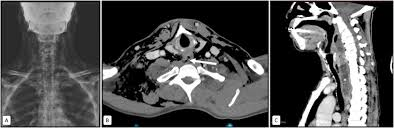

Se usa una amplia gama de técnicas de adquisición de imágenes para poder ver dentro del cuerpo y determinar el alcance de un sarcoma óseo y establecer la presencia o ausencia de enfermedad metastásica distante.

1. Rayos X

2. Resonancia magnética

3. TAC contrastado

4. Gammagrafía Ósea